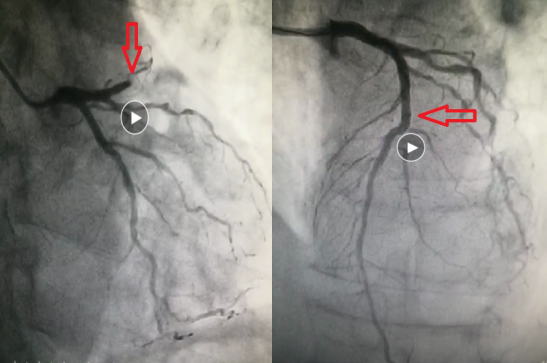

李主任立即按照胸痛救治流程,立即给予了心梗一包药并启动导管室,开通绿色通道;通知导管室人员进行抢救,完善术前准备。患者被紧急推送入导管室行冠状动脉造影术,造影结果显示:左冠脉前降支近段闭塞。立即用导丝通过闭塞病变,在预扩球囊经过闭塞处时,心电监护显示加速性室性自主心律,之后出现窦性心动过缓,心率50次/分,血压80/50mmHg。立即予阿托品1mg静脉注射,去甲肾上腺素静脉滴注,约1分钟,患者心律升至90次/分,血压升至130/89mmHg,患者胸部闷症状逐渐缓解。撤出预扩球囊,予欣维宁冠脉内推注,前降支中段可见80-90%的弥漫性狭窄,予前降支植入支架两枚。手术很成功。整个过程只花了短短45分钟,患者安返CCU病房。